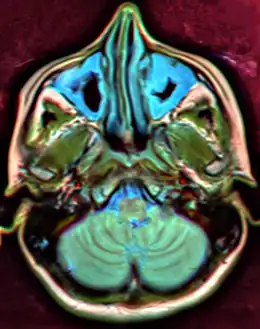

Maxillary sinusitis caused by a dental infection associated with periorbital cellulitis